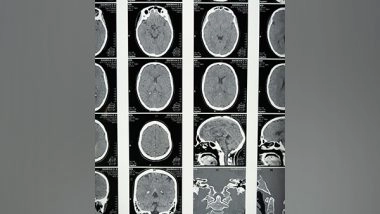

Researchers at the University of Waterloo and the University of Toronto have partnered with St. Michael's Hospital in Toronto to analyze MRI data from multiple GBM sufferers. They're using machine learning to fully analyze a patient's tumour, to better predict cancer progression.

Researchers analyzed two sets of MRIs from each of five anonymous patients suffering from GBM. The patients underwent extensive MRIs, waited several months, and then received a second set of MRIs. Because these patients, for undisclosed reasons, chose not to receive any treatment or intervention during this time, their MRIs provided the scientists with a unique opportunity to understand how GBM grows when left unchecked.

The researchers used a deep learning model to turn the MRI data into patient-specific parameter estimates that inform a predictive model for GBM growth. This technique was applied to patients' and synthetic tumours, for which the true characteristics were known, enabling them to validate the model.